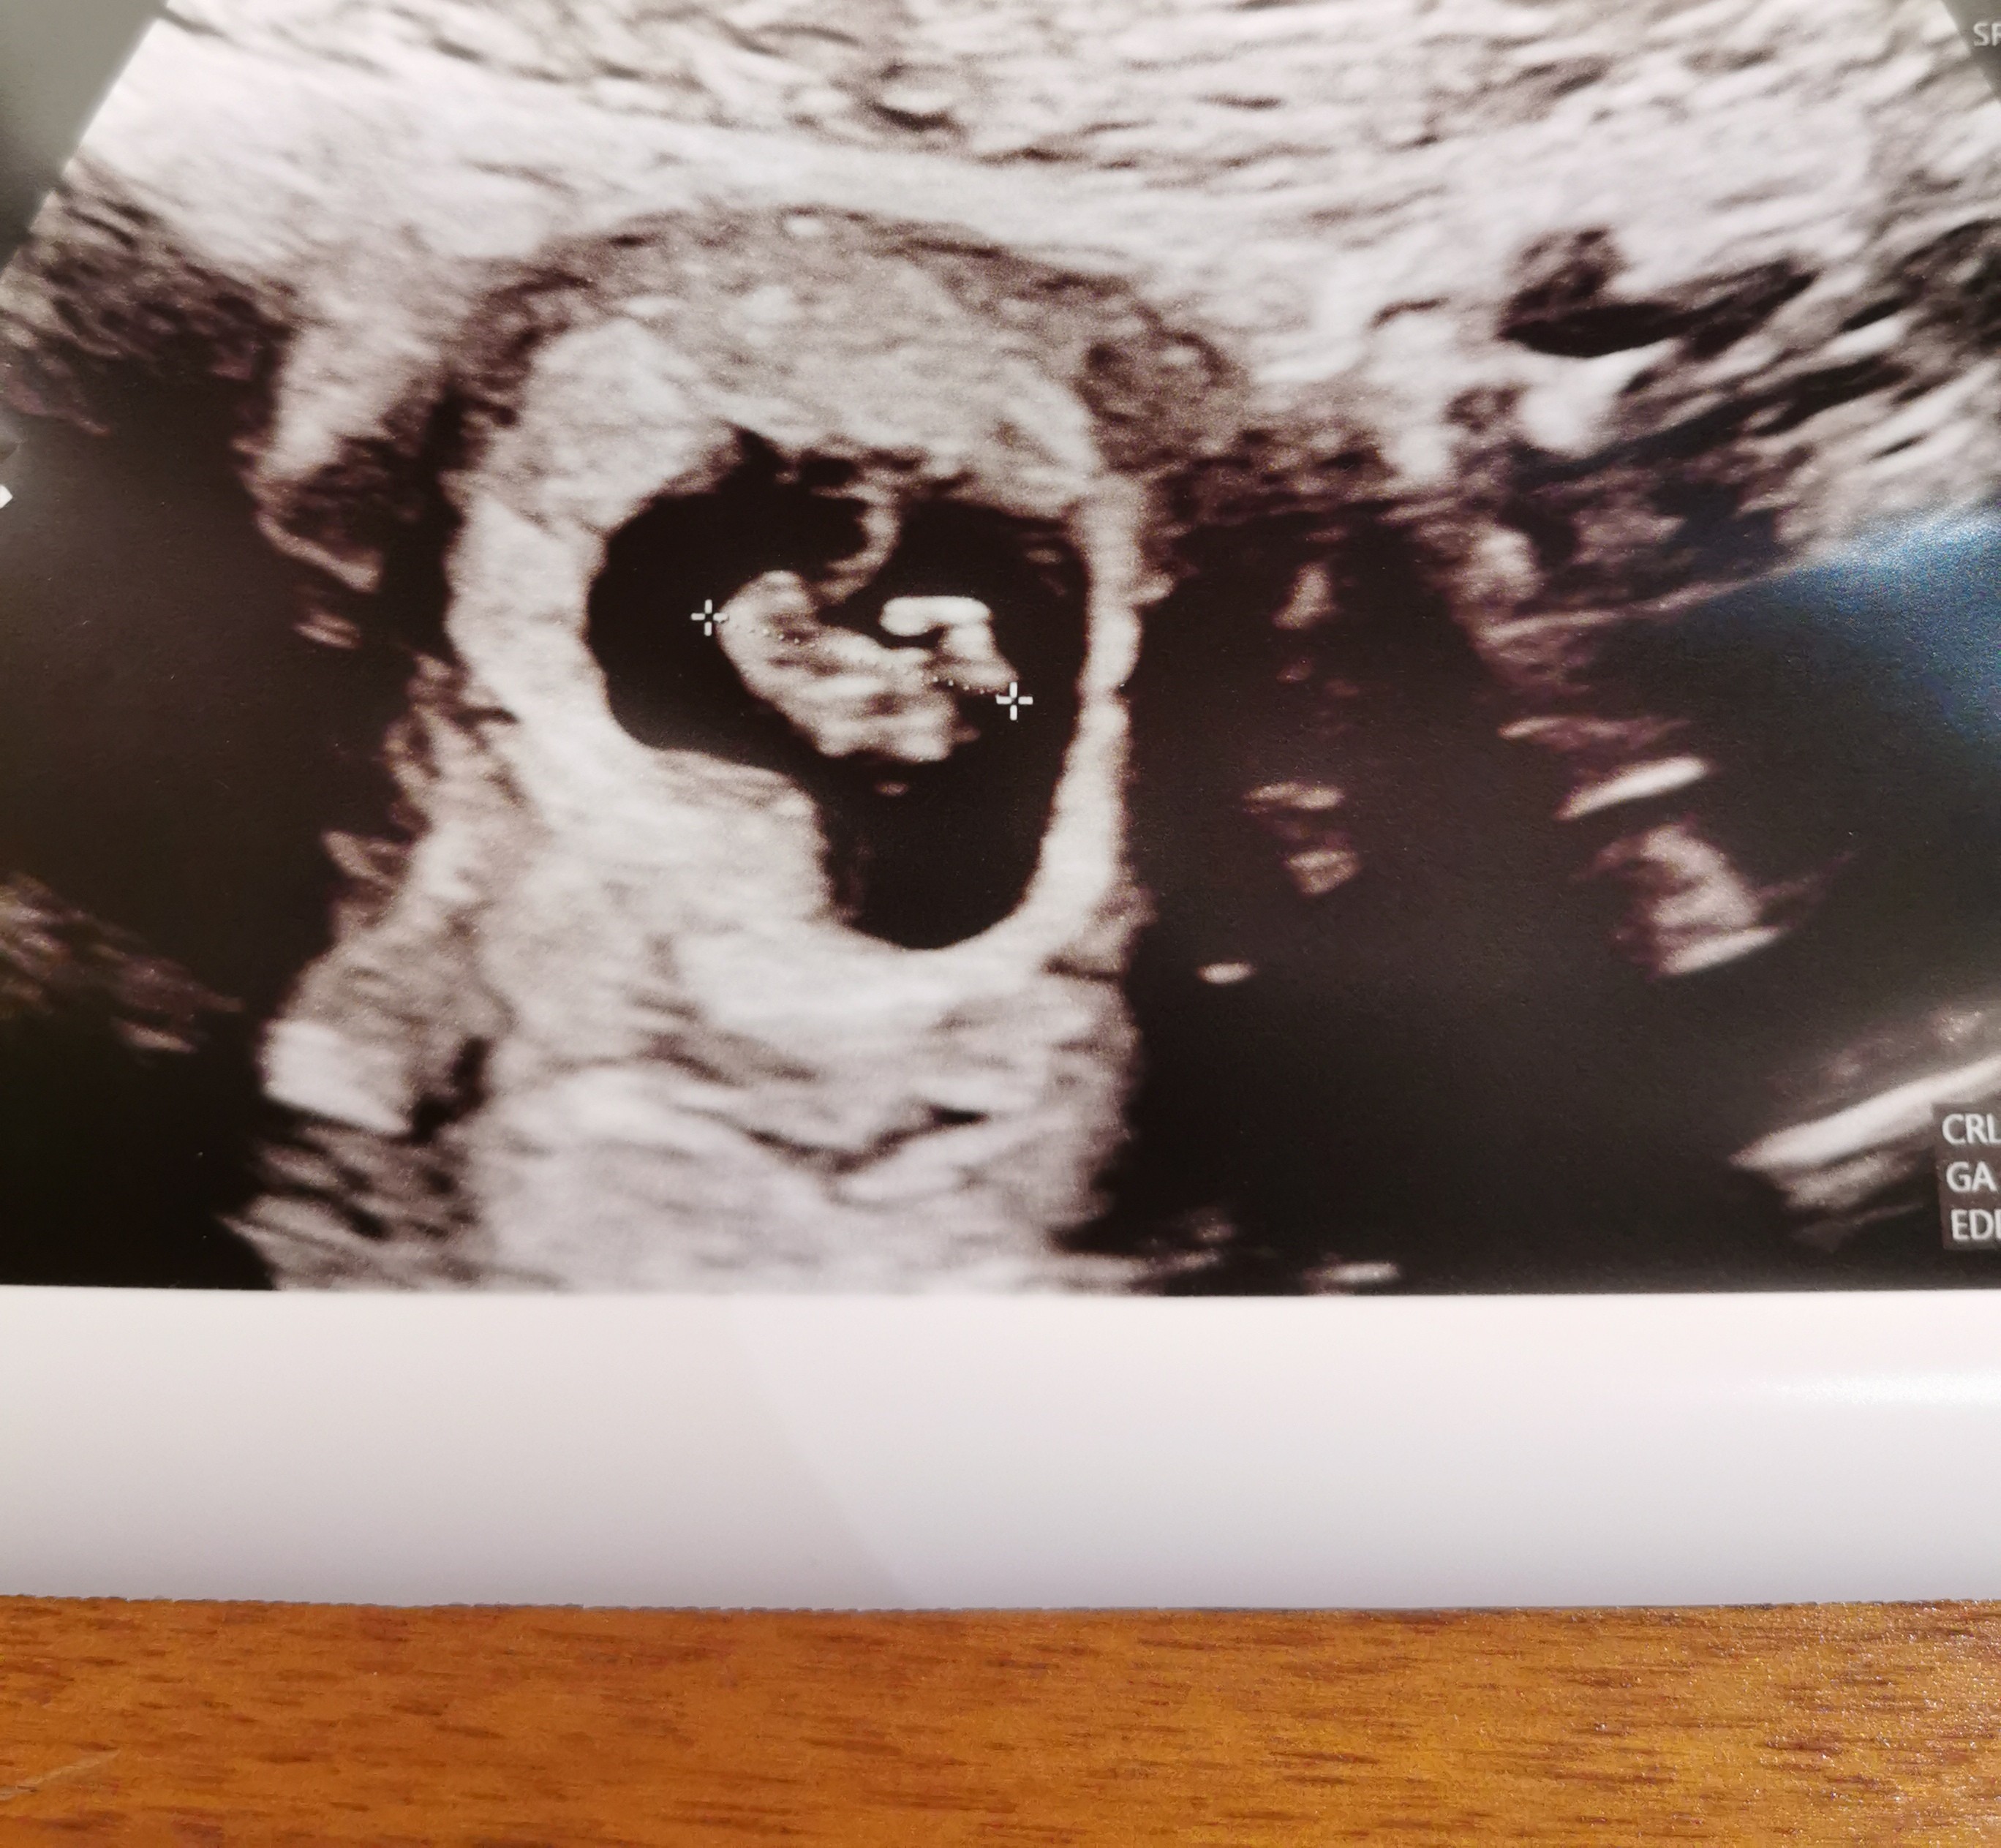

Cześć dziewczyny, nie było mnie tu bardzo długo i nie jestem wstanie nadrobić wszystkich wiadomości, wybaczcie! Witam wszystkie nowe kobietki i życzę wszystkiego dobrego! Nie było mnie, bo tak mnie od dwóch tygodni męczą mdlosci, że ledwo funkcjonuje, raz na kilka dni zdarzy się dzień, że czuję się lepiej i staram się wtedy ogarnąć coś w domu, a tak to od rana do wieczora non stop mdlosci, potrafią mnie wybudzać nawet w nocy 🥺 byłam u lekarza na pierwszej wizycie, na usg był równo tydzień 8 a wg ostatniej miesiączki 8+2, termin na 11 kwietnia a wg om na 9 kwietnia, następną wizyta w równo 12 tygodniu, będę robić badania na płeć i nifty, tu w Belgii są za darmo, na pierwszej wizycie widziałam i słyszałam serduszko, takie emocje że się popłakaliśmy, usg było przez brzuch, ale ani mnie nie zważyła ani nie zleciła żadnych badań krwi, dziwne, jak to wygląda w Polsce?